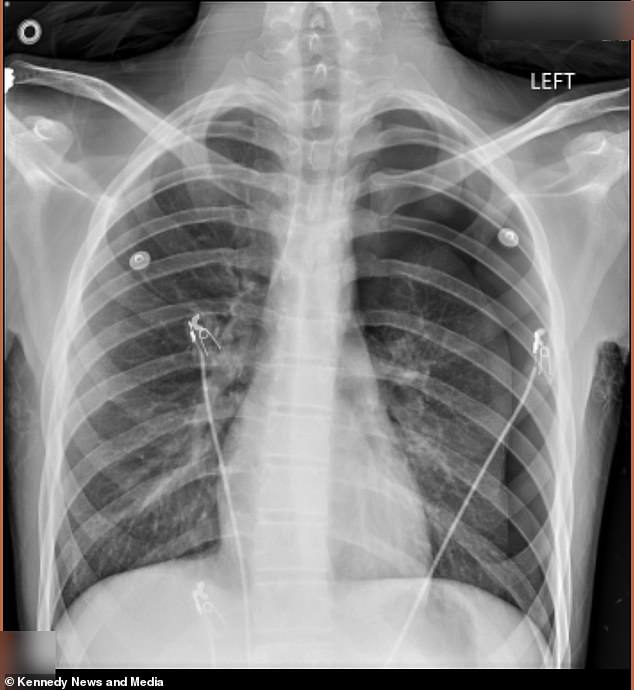

Doctors found that 50 percent of his left lung had collapsed, also called a pneumothorax, which occurs when air gets inside the chest cavity and creates pressure.

Dodge’s pneumothorax was so advanced that doctors had to surgically insert an 18-inch tube into his chest to get rid of the extra air and allow his lung to re-expand. However, the teen kept vaping without his mother’s knowledge.

Pictured above is the x-ray scan showing Dodge’s collapsed left lung. Doctors said that after the second time, he could have died in the hospital lobby